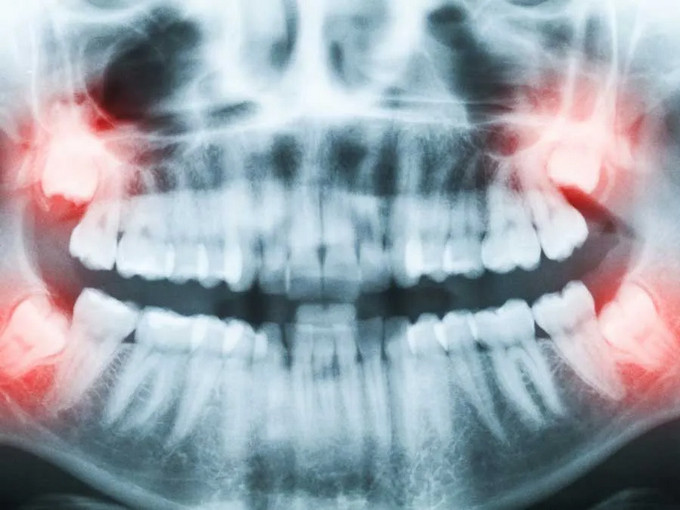

不少患者因埋伏牙、阻生牙飽受牙齦腫痛、牙列擁擠等問題困擾,但又因擔(dān)心手術(shù)疼痛、創(chuàng)傷大而遲遲不敢治療。事實(shí)上,埋伏牙不及時(shí)處理,不僅會(huì)反復(fù)感染,還可能損害鄰牙、影響口腔健康,甚至引發(fā)囊腫及頜面部間隙感染等嚴(yán)重問題。

門診采用CBCT三維影像技術(shù),精準(zhǔn)定位埋伏牙位置、形態(tài)及與周圍神經(jīng)關(guān)系。根據(jù)患者口腔條件、埋伏牙位置及風(fēng)險(xiǎn)因素,定制個(gè)性化精準(zhǔn)拔牙方案,減少不必要的創(chuàng)傷與風(fēng)險(xiǎn)。